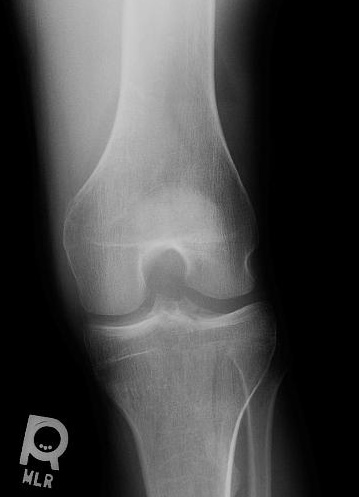

When there is an intraarticular fracture of the tibial plateau or of one of the femoral condyles, bone marrow (mostly fat) migrates from the marrow space into the joint space. With fracture, blood also escapes, and a lipohemarthrosis is produced. Fat is less dense than blood, and it layers superior to it, producing the change in radiographic density referred to as a fat-blood interface (FBI sign).

CASE 1: These four radiographs are from a 50 year old male who fell 1 day prior to presentation. There is a tibial plateau fracture and a lipohemarthrosis. Click on each image for a larger view and notice the location of the fat-fluid level.

CLICK TO ENLARGE CLICK TO ENLARGE